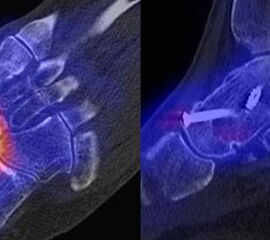

Bildbeispiele Arthrose für Arthrosen sind in den Abbildungen 1.1. bis 1.4. dargestellt:

Abbildung 1.1. zeigt eine isolierte aktivierte fortgeschrittene Arthrose des 3. Lisfranc-Gelenkes am linken Fuß. Klinisch bestanden belastungsabhängige Schmerzen plantar im Mittel-/Vorfuß.

Abbildung 1.2. zeigt eine ausgedehnte posttraumatische Arthrose im linken OSG. Der metabolische Focus liegt in der Hauptbelastungszone.

Zum Lesen der Bildbeschreibung und zur Vollansicht bitte die Bilder anklicken. Bilder: H. C. Rischke

Abbildung 1.3.

Abbildung 1.3.a und Abbildung 1.3.b: Der Patient hatte einen Skiunfall vor 40 Jahren mit distaler Tibiatrümmerfraktur. Nachfolgend Entwicklung einer Osteomyelitis; Operation mit Implantation eines Knochenspans. Klinisch rezidivierende Schwellungen des oberen Sprunggelenkes, bekannte Tibiafehlstellung. Frage nach Osteomyelitis, Status der Arthrose. Man sieht in Abbildung 1.3.a in der distalen Tibiametaphyse im CT Strukturveränderungen, die zu einer abgelaufenen Osteomyelitis passen - szintigraphisch hier keinerlei Anreicherungen und somit kein Infektverdacht, jedoch Nachweis einer aktivierten oberen und unteren Sprunggelenksarthrose.

Abbildung 1.4.

Abbildung 1.4.a und Abbildung 1.4.b: Klinisch Verdacht auf talonaviculare Anschlussarthrose links bei Z. n. Fraktur im Bereich des linken Sprunggelenkes vor 17 Jahren. und Z. n. Oberschenkel-Unterschenkelfraktur vor über 40 Jahren. Obwohl auch CT-morphologisch im OSG arthrotische Veränderungen bestehen, ist nur die Arthrose im USG metabolisch aktiv bzw. als Ursache der Schmerzen einzustufen. Im Bereich des Talonavicular-Gelenkes - entgegen der klinischen Verdachtsdiagnose - kein erhöhter Metabolismus.